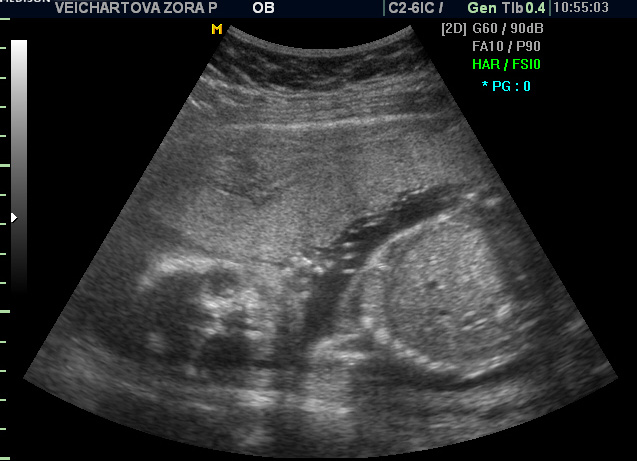

Ještě fotečka z 30. tt..

Ahoj kočky, zdravím po dlouhé době. Jak se máte? já teď nemám "čárku" - třeba ještě přijde. U malýho jsem ji měla :D dodatečně přidávám utz - má to být princezna, čímž mě docela odzbrojili, počítala jsem s druhým klukem :D foto pupenda někdy přidám, ale vyvalí se jen navečer a pak se zase stáhne :D už máte všechno zařízené? :-)